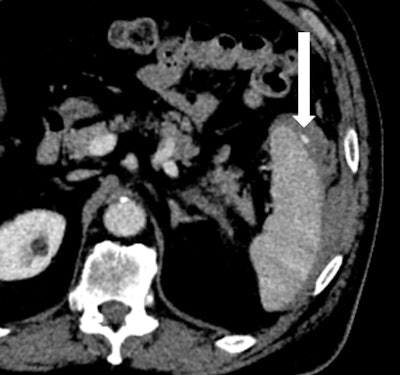

After initial resuscitation and focused assessment with sonography in trauma (FAST), he underwent a CT of the chest, abdomen, and pelvis that revealed a 1.4-cm grade III splenic laceration near the anterior lip associated with a focus of contrast extravasation. The exam also revealed an associated subcapsular hematoma larger than 50% of the surface area of the spleen, with hemorrhage tracking along the left paracolic gutter into the pelvis (figures 1A and 1B). The pancreas appeared unremarkable on this CT (figure 2).